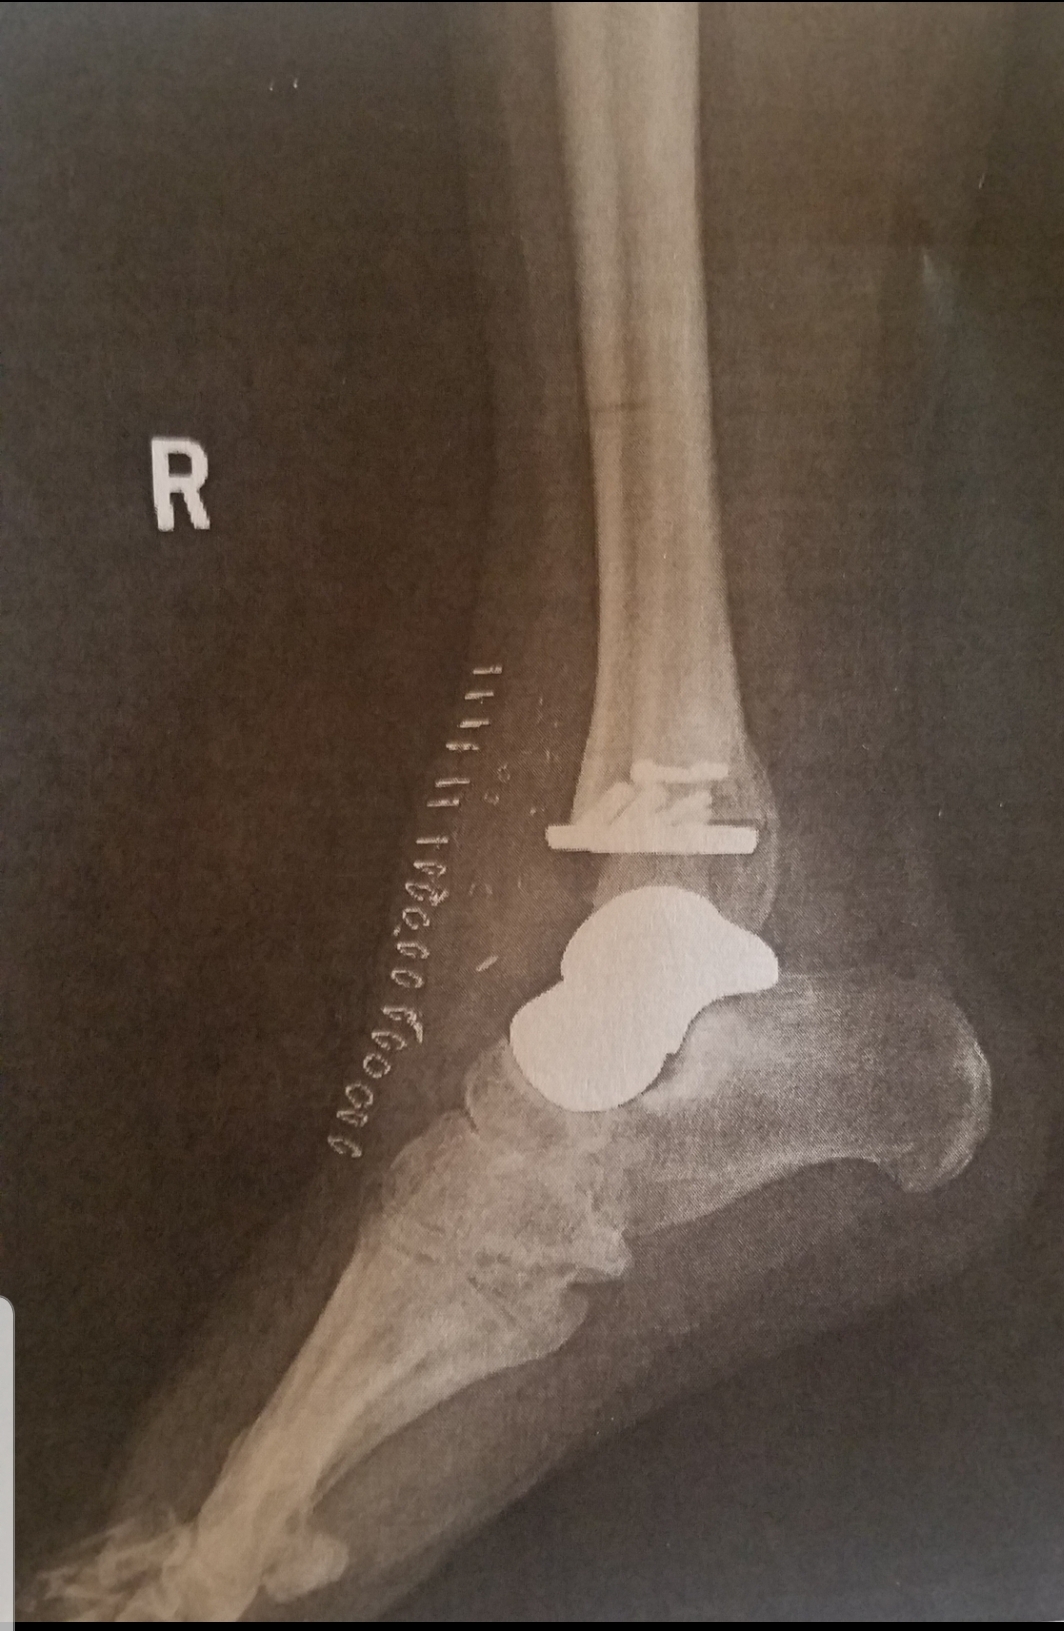

The 3D printed talus is in gold with Tara’s cadence ankle on top in white.

Post-surgery X-ray of Tara’s ankle.

In North Carolina, a 3D scan was done of her left ankle from which a mirror 3D implant was made for her right ankle.  On Feb. 28, 2019, Michaud had her ankle replaced and the 3D talus implanted.